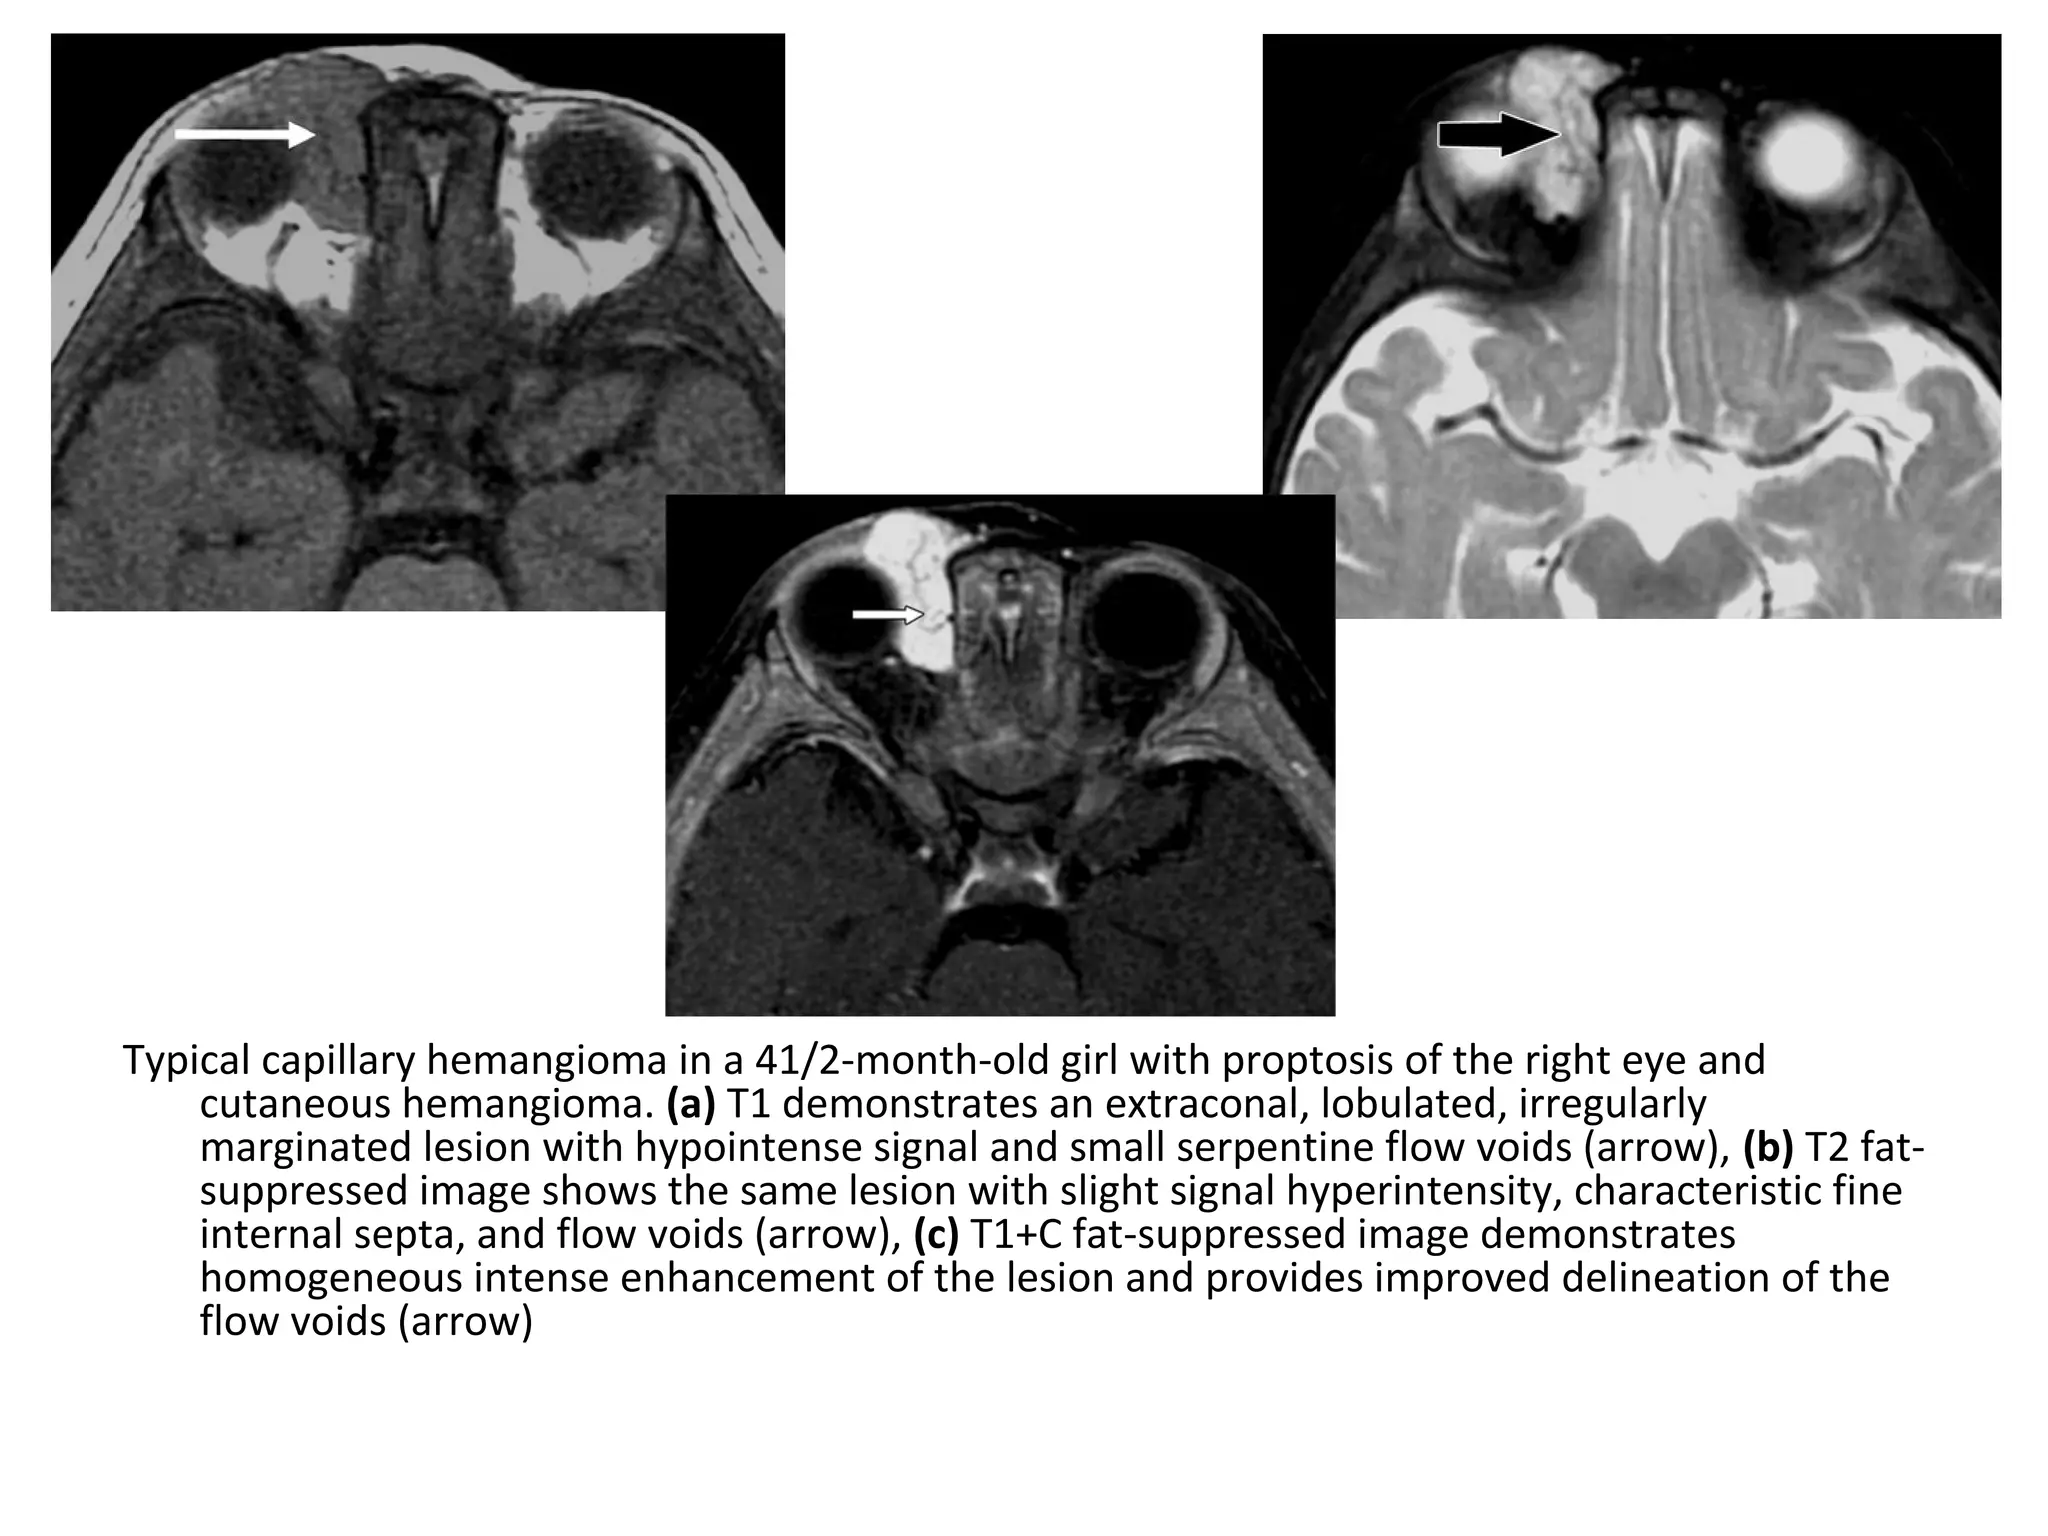

Typical capillary hemangioma in a 41/2-month-old girl with proptosis of the right eye and

cutaneous hemangioma. (a) T1 demonstrates an extraconal, lobulated, irregularly

marginated lesion with hypointense signal and small serpentine flow voids (arrow), (b) T2 fat-

suppressed image shows the same lesion with slight signal hyperintensity, characteristic fine

internal septa, and flow voids (arrow), (c) T1+C fat-suppressed image demonstrates

homogeneous intense enhancement of the lesion and provides improved delineation of the

flow voids (arrow)